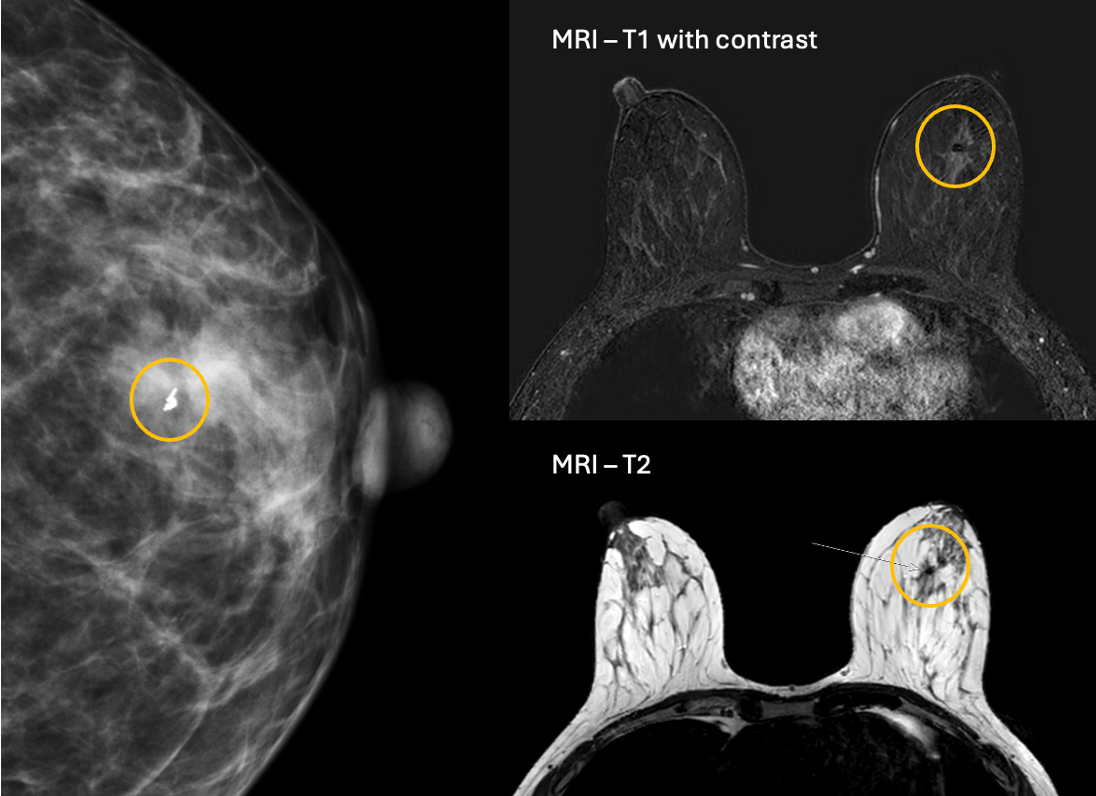

Breast biopsy marker brochureMammogram and MRI showing Gold Anchor implanted in breast to mark a biopsy site

The majority of the suspicious lesions detected by screening mammography are small nonpalpable lesions, i.e. mass lesions or calcifications. Biopsy are performed to differentiate between benign and malignant lesions and decide if surgical removal is needed.

It is helpful to mark these lesions with a marker (clip) which can be implanted during the initial biopsy procedure or in a second step. Clip-marking is done in order to prove the correct location of the biopsy and to guide the surgeon for the excision.